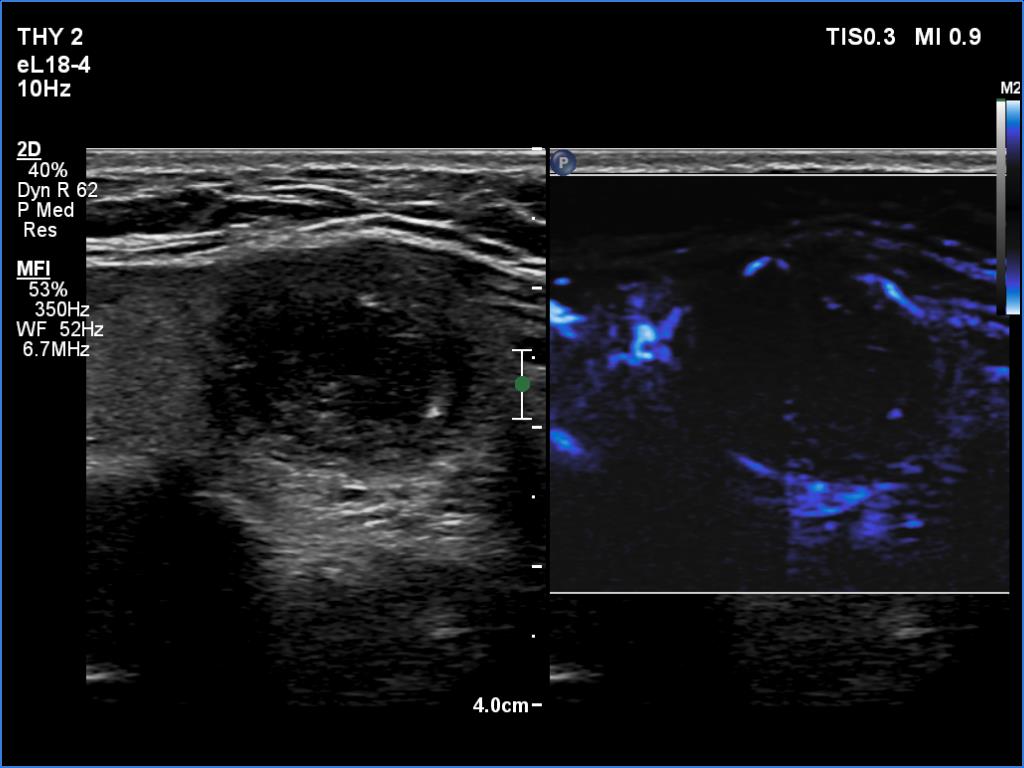

Ultrasonography revealed an echonormal thyroid. There was dominantly moderately hypoechoic nodule in the right lobe. Some parts of the lesion were deeply hypoechoic, and a few small cystic chambers were also within. The nodule presented with irregular shape and borders and had intranodular echogenic figures, primarily granules.

It is worth comparing the images recorded by using different settings. By using harmonization, we lose the details of very hypoechoic areas. Essentially, the latter seem to be anechoic.